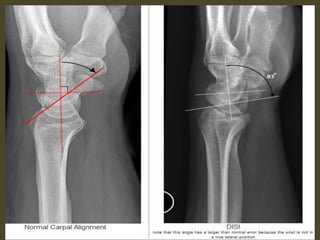

DISI deformity.

DISI.

Volar intercalated segmental instability(VISI).

VISI with volar tilting of the lunate.

VISI with luno-triquetrum ligament tear and volar tilting of the lunate.

VISI deformity secondary to Lunotriquetral ligament tear.